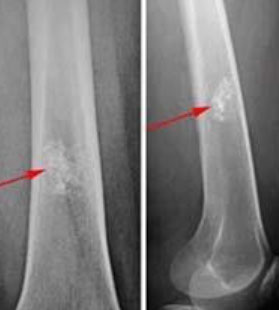

Parosteal osteosarcoma

Periosteal osteosarcoma

Surface osteosarcomas can be parosteal or periosteal and are MC in women

Parosteal: well-differentiated juxtacortical tumors sticking out like a mushroom on the posterior part of proximal femur; have irregular arrangement of woven (immature) bone lacking osteoblastic lining; and is surrounded by spindle cells

Imaging: no Codman's triangle; center is more dense than periphery, but look out for the posterior mushroom!, invade cortex to medullary cavity

- spindle cells look deceptively like normal fibroblasts (minimal atypical features), they microscopicaaly grow between well formed parallel arranged bony trabeculae

- cartilagenous differentiation seen in ~1/2 cases

- intraosseous part of tumor is completely cut off from the normal bone marrow

- generally has an excellent px, but can get complicated (dedifferentiated) if not completely excised

Periosteal: intermed.-grade with moderately differentiated, atypical (high-grade) cartilage covered in small rim of mesenchymal cells (immature, round to spindle-shaped with central hyperchromatic vesicular nuclei) which is further covered by periosteum, grossly more fusiform

- 2-3% of osteosarcomas, occurring on the bone surface of long bones in young pts

Imaging: fusiform, broad-based radiolucency on bone surface; Codman's triangle

Tx: neoadjuvant tx and en bloc excision

- should grade response to neoadjuvant tx (>95% tumor necrosis is good)

Px: better than that of usual high-grade osteosarcoma; can get mets to lung or other bones